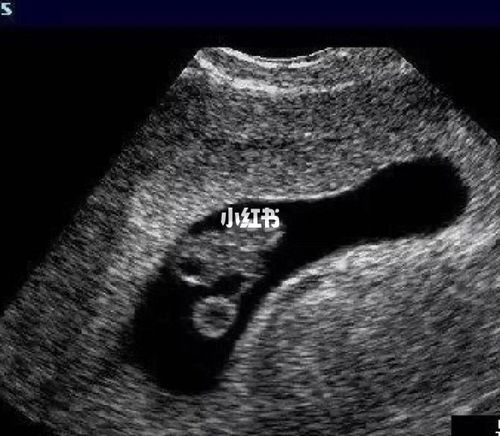

胎儿nt超声标准切面图

胎儿nt超声标准切面图,nt标准切面示意图

胎儿基础切面01-nt_超声

nt标准切面示意图

胎儿nt测量标准切面图

超声nt标准切面图

nt测量标准切面超声图